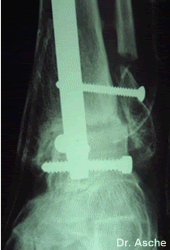

Minimal invasive Arthrodese mit Kompressionsnagel

Postoperative seitliche Röntgenaufnahme